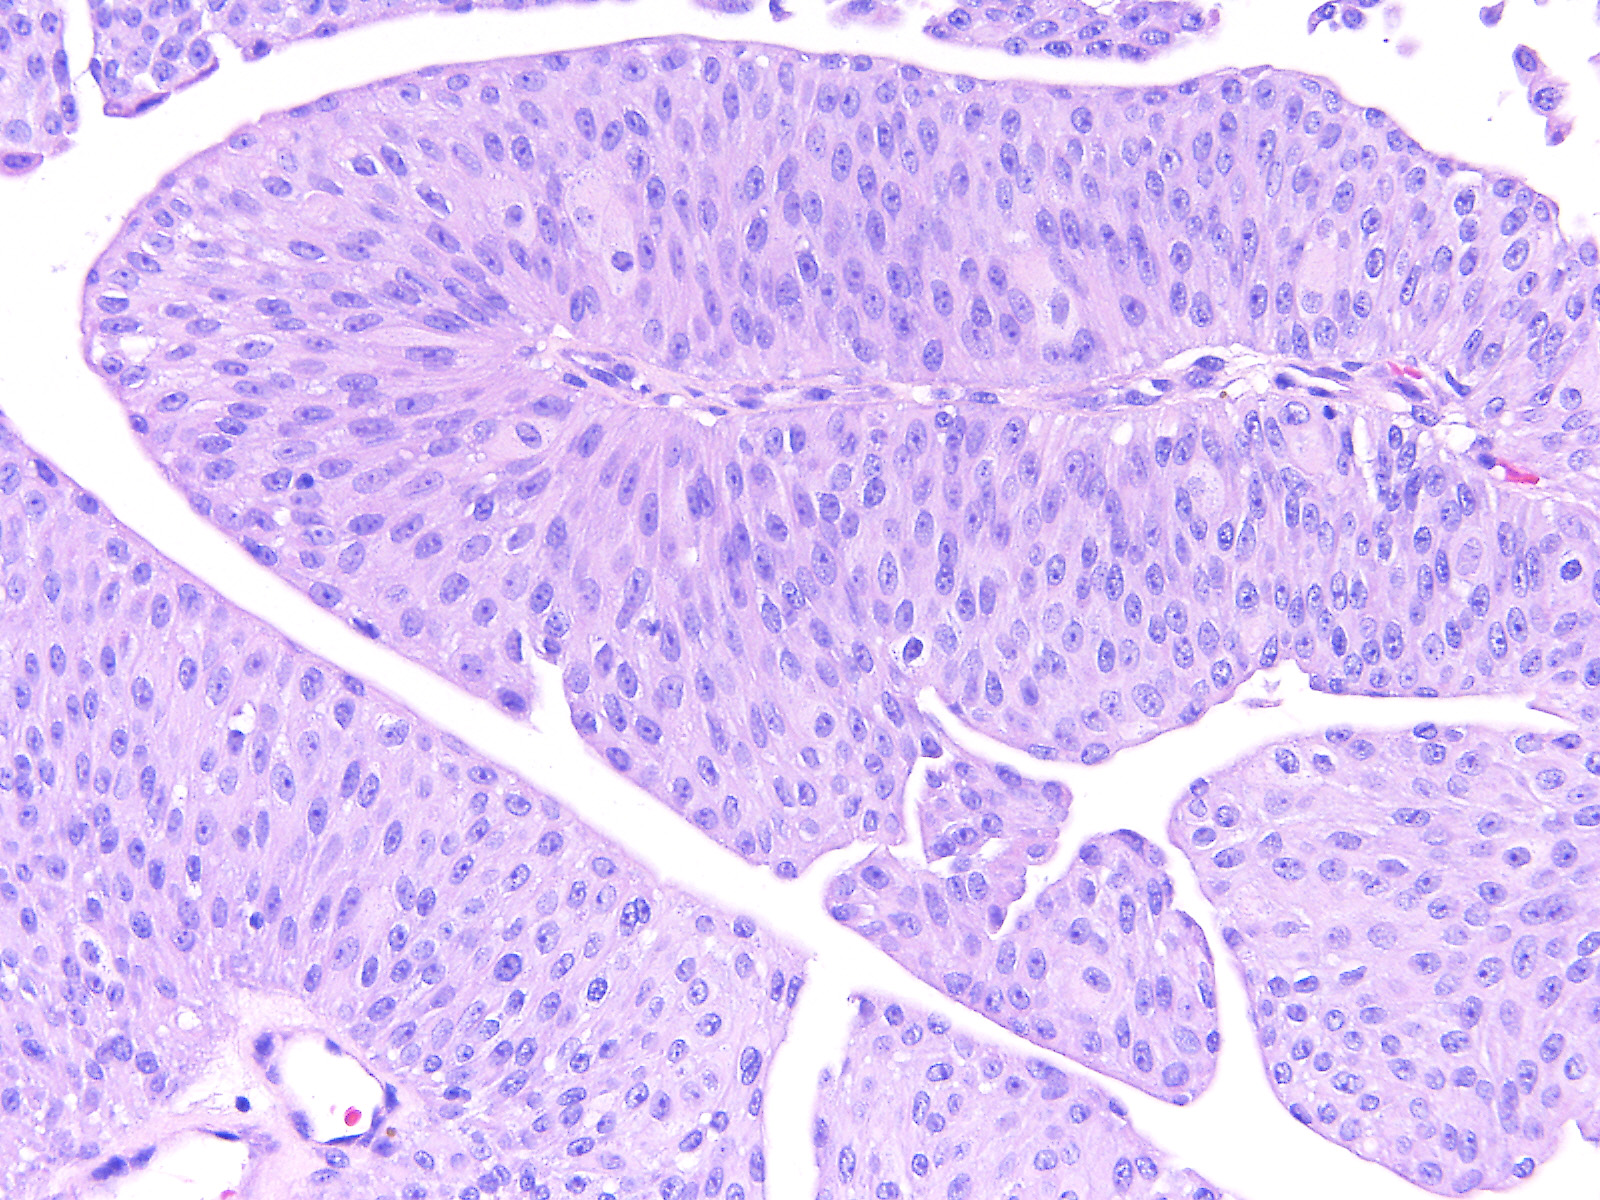

Bladder Papillary Lesions

Case ID: 559